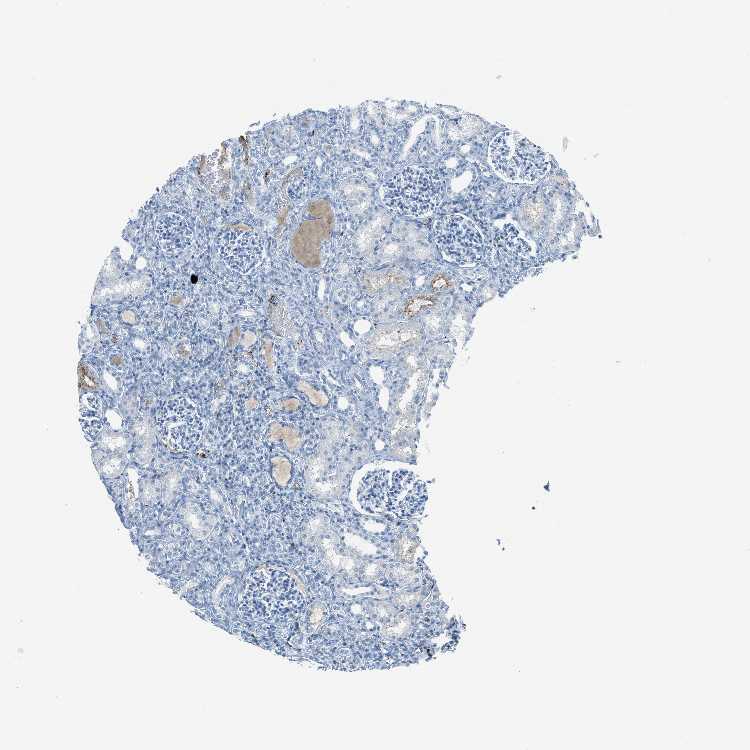

KIDNEY - Antibody stainingi

Antibody staining in the annotated cell types in the current human tissue is reported as not detected, low, medium, or high, based on conventional immunohistochemistry profiling in selected tissues. This score is based on the combination of the staining intensity and fraction of stained cells.

Each image is clickable and will lead to virtual microscopy that enables deeper exploration of all samples and also displays staining intensity scores, fraction scores and subcellular localization as well as patient and tissue information for each sample.

Antibody HPA008354Antibody CAB017624

Cells in glomeruli Not detectedNot detected

Cells in tubules LowLow